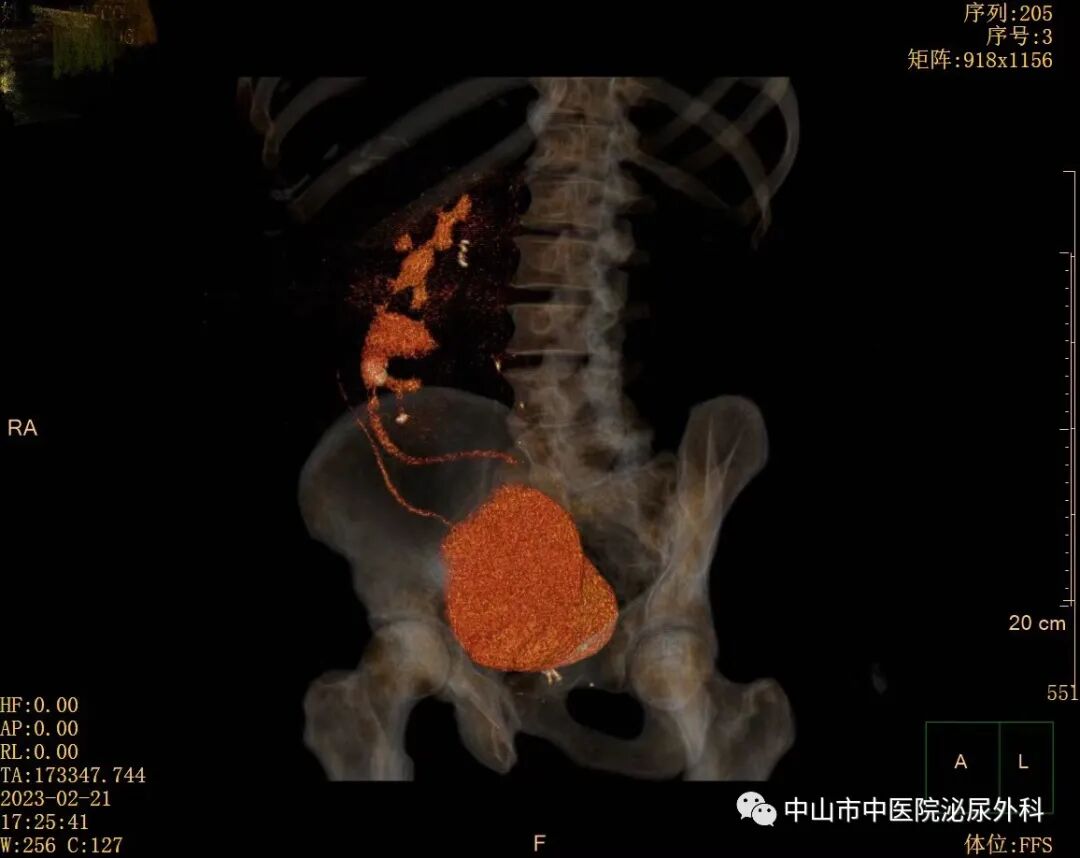

术前影像资料

输尿管鞘是什么一期软镜治疗罕见交叉异位肾并结石(术中使用一次性末端可弯负压清石鞘)_https://www.jmylbn.com_新闻资讯_第3张

输尿管鞘是什么一期软镜治疗罕见交叉异位肾并结石(术中使用一次性末端可弯负压清石鞘)_https://www.jmylbn.com_新闻资讯_第4张